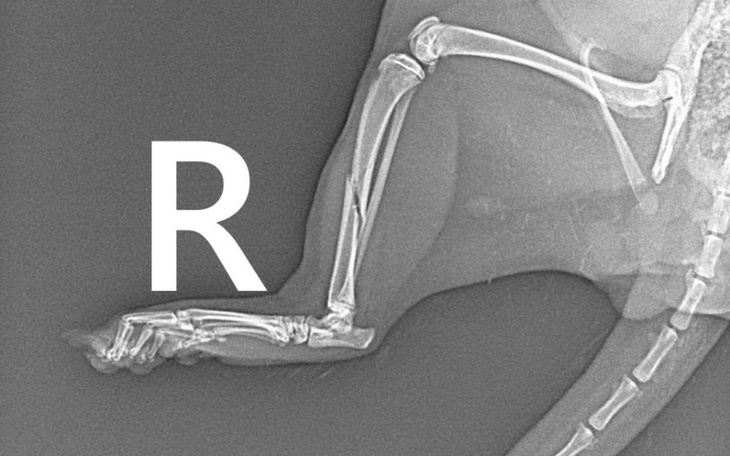

Nie wiem jak pisać chwytajace za serce teksty więc poprostu napisze co i jak. Od jakiegoś czasu mieszkają u mnie dwie fretki, bracia, Ptyś i Pączek. Niestetyw niedzielę zauważyłam, że Ptyś nie staje na tylną nóżkę, myślałam, że możenadwyrężył czy coś. W poniedziałek nie było żadnej poprawy więc zaczęłam dzwonić po lekarzach, wizytę miałam dzisiaj (17.09), okazało się, że Ptyś ma złamaną łapkę i potrzebna jest pilna operacja. Nie mogę wziąć "pożyczki" od Mediraty bo nie mam dochodu. Zostaje mi prosić was o pomoc, nawet drobna kwota wiele dla mnie znaczy.